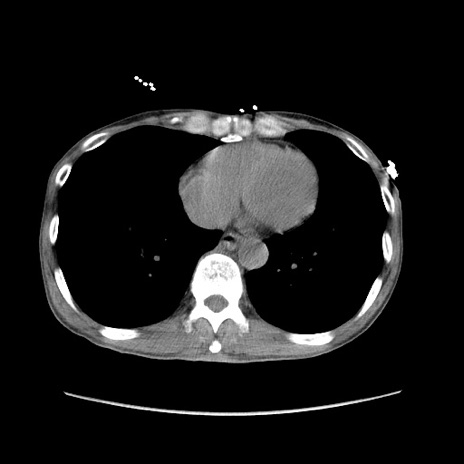

冠状断像

症例11(横断像)

【症例】 60歳代男性

【主訴】 下腹部痛

【現病歴】 本日夜中より下腹部痛の症状認め、受診。

【既往歴】 膀胱癌(膀胱全摘+尿管皮膚瘻術) 、胃癌術後

【身体所見】 BT 35.3℃、PR 58/min、BP 136/98mHg、腹部平坦、軟、腸蠕動音±、ストマ留置あり、左上腹部~正中部に圧痛あり、反跳痛なし。

【データ】WBC 5100、CRP0.01